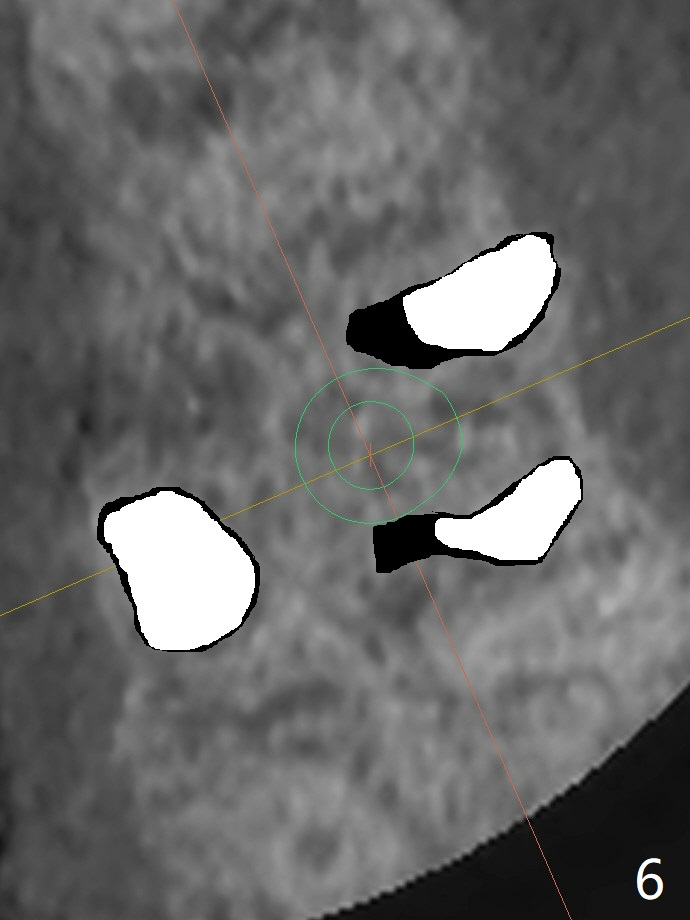

A 48-year-old man returns for implant at #14 after endo consult (Fig.1). The tooth appears to have fractured subgingival palatal (Fig.2,3 P). The furca is thin (Fig.3 *). A 5x10 mm implant will be placed slightly away palatal because of bone loss (Fig.4). Since the mesiobuccal (Fig.5 MB) and distobuccal (DB) sockets are close to the osteotomy (green), gauze with 1:50,000 Epinephrine (to reduce hemorrhage during sinus lift) will be placed away from the osteotomy (Fig.6 white area). In fact socket shield is conducted palatal.